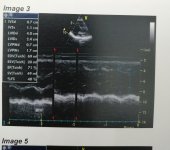

عملت ايكو هل في حاجه في الايكو تستدعي الذهاب لطبيب قلب و ارجو شرحها ان وجدت؟ و شكرا

عملت ايكو هل في حاجه في الايكو تستدعي الذهاب لطبيب قلب و ارجو شرحها ان وجدت؟ و شكرا